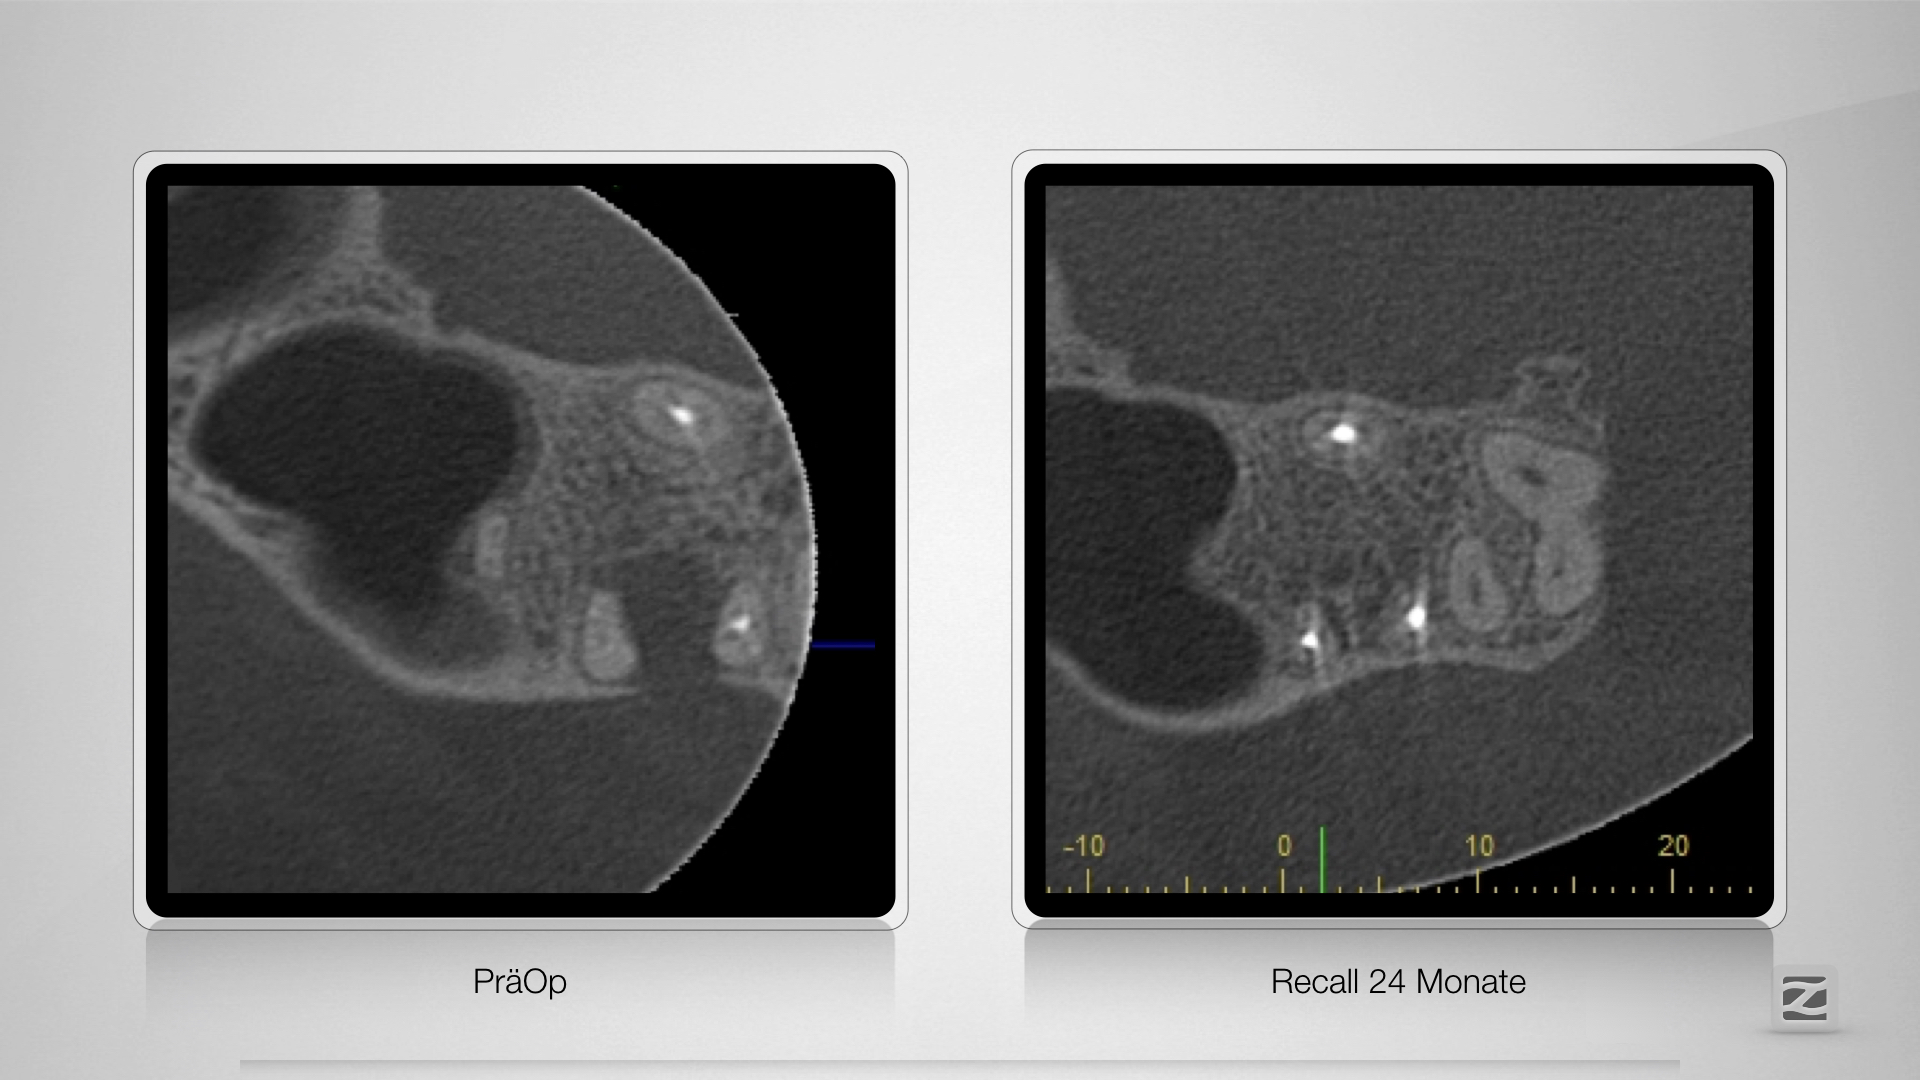

26D.011

Große Lyse